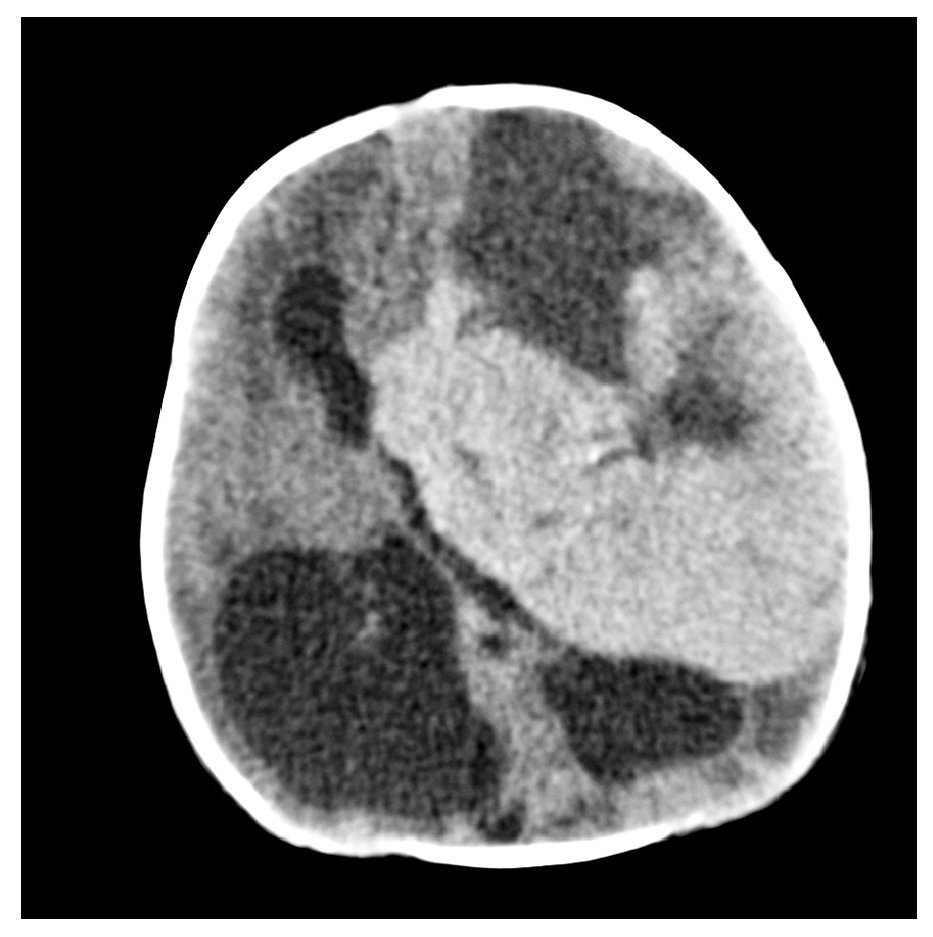

Gestante en el séptimo mes del embarazo. En ecografía de control se detecta hidrocefalia.

Fig. 1.